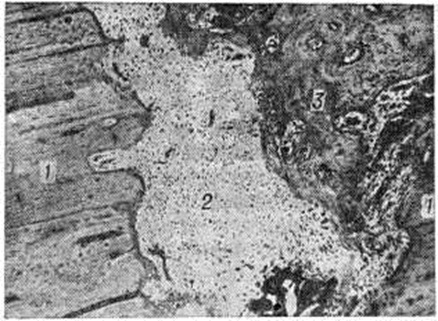

При точном сопоставлении отломков возможно прямое костное сращение с помощью интермедиарной костной мозоли, что именуют первичным костным сращением. Когда сращение отломков наступает после предварительного соединения их костно-хрящевой провизорной мозолью, на основе которой постепенно будет формироваться окончательная интермедиарная костная мозоль, говорят о вторичном костном сращении. Первичное костное сращение может произойти только в строго определённых условиях: при достаточном кровоснабжении отломков, точности их сопоставления, достаточности их обездвижения. Микрофотографии кости при первичном сращении в разные сроки консолидации представлены на рисунок 1 и 2.

В подавляющем большинстве случаев из-за трудностей обеспечения всех необходимых условий костное сращение бывает вторичным, при котором в разные сроки (но не ранее 6—8-й недель и до многих месяцев) после Переломы формируется окончательная костная мозоль. Такой вариант является проявлением адаптационных механизмов организма, направленных на восстановление целости кости в неблагоприятных условиях для заживления костных ран. Невозможность мобилизации таких приспособительных реакций приводит к несращению отломков повреждённой кости. Наиболее благоприятными для проявления адаптационных возможностей организма являются Переломы тех отделов костей, где имеется надкостница и окружающий её мышечный массив, например, диафизарные Переломы трубчатых костей. Переломы лишённых надкостницы эпифизов костей при отсутствии условий, необходимых для первичного костного сращения, не могут срастаться путём приспособительного вторичного костного сращения, поэтому без применения остеосинтеза отломки часто не срастаются, например, при медиальных Переломы шейки бедренной кости. Микрофотография кости при вторичном сращении представлена на рисунок 3.